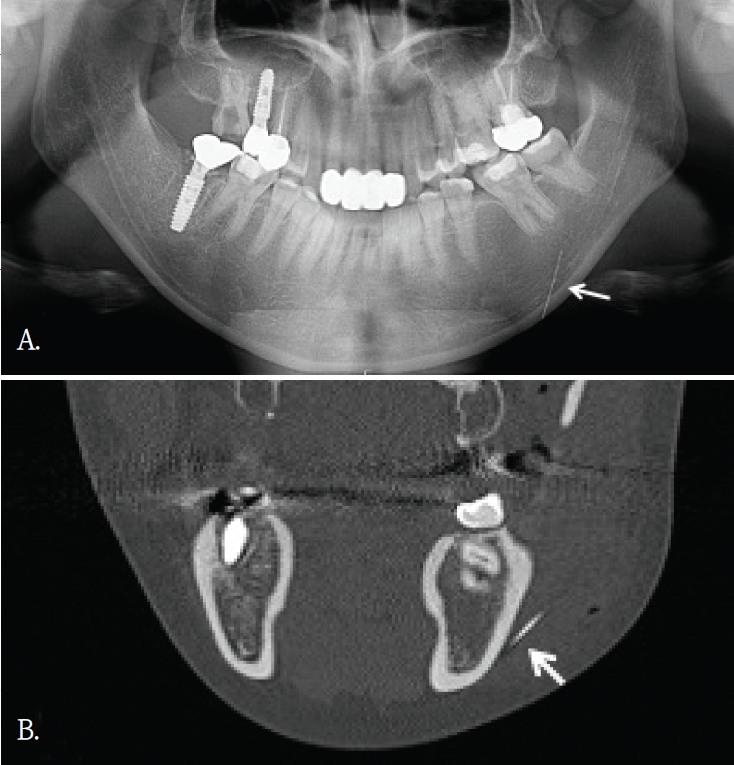

Fig. 2.

A. Panoramic radiograph shows no definite abnormality in the maxilla. B. Axial cone-beam computed tomographic (CBCT) image shows crescent-shaped radiopaque foreign bodies along the anterior walls of the bilateral maxillary sinuses (arrows). C. Cross-sectional CBCT image also demonstrates the same findings on a different plane (arrows).

50대 여자환자가 상악 전치부 임플란트치료를 위해서 콘빔 CT검사를 시행하였다. 파노라마방사선영상에서는 해당 부위에 특이 소견이 뚜렷하지 않았다(Fig. 2A). 그러나 콘빔CT의 축상면 및 횡단면 영상에서 양측 상악동 전벽에 인접한 안면 피하 연조직을 따라, 반달모양의 경계가 명확하고 내부가 균질한 음영을 보이는 구조물이 관찰되었다(Figs. 2B and C). 해당 소견은 주된 촬영 목적과 무관하였고 양측에서 대칭적으로 관찰되었으며 관련 증상이 동반되지 않았다. 임상 소견 및 영상 소견을 종합할 때 병변 가능성은 낮다고 판단하였고, 위치와 형태를 고려하여 피하에 주입된 미용필러에 의한 소견으로 판단하였다. 이에 추가 처치는 시행하지 않았다.

한편, 안면미용시술을 받은 환자들이 치과에 많이 내원하면서 우연히 발견되는 이물질 소견 중 하나가 미용 필러이다[9]. 치과의사들에게 아직은 익숙하지 않은 방사선영상 소견이고 부위도 치아나 악골이 아닌 연조직부위에서 관찰되기에 영상 판독에서 배제될 가능성이 있다. 미용필러도 파노라마방사선 영상에서보다는 콘빔CT영상에서 위치나 형태, 양상을 잘 관찰할 수 있다.